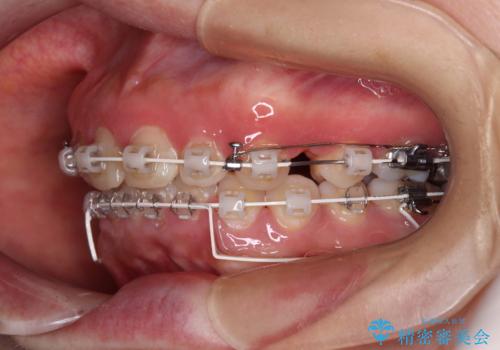

- 矯正装置

- 審美装置

骨格的に上顎が前方にあり、上顎のみの抜歯矯正のため、期間はかかることが予想されましたが、スムーズに移動してくれたおかげで、2年弱の短期間で終えることができました。